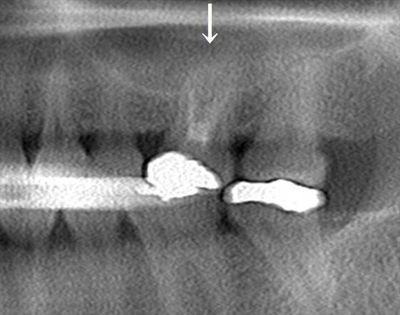

左上第一大臼歯の再根管治療を行いました。2019.08.20

本日、仮封を除去したところ、排膿はほとんどありませんでしたので

根管充填まで進みます。

根管充填を行う際のファイルサイズ(ヤスリのサイズ)を決定します。(根管長測定)